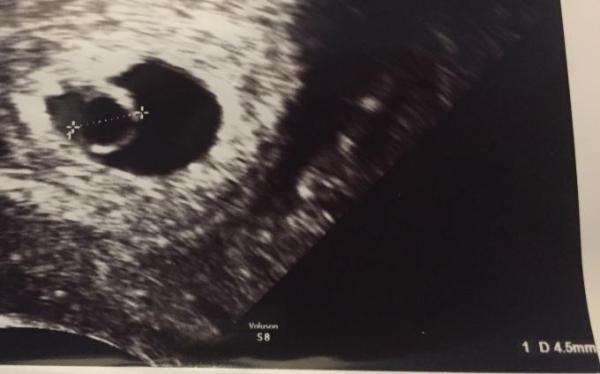

Hallo zusammen Ab wann war bei euch der Embryo auf dem Ultraschall ersichtlich? Ich war bei 5+6 beim FA und man sah die Fruchthöhle mit dem Dottersack, aber ohne Embryo....

Bild zu Ab wann Embryo ersichtlich? - Schwanger - wer noch? Rund um die Schwangerschaft

Bei mir sah man das Kleine erst in der 7. SSW, ich hatte nen kleinen Eckenhocker. Dein Bild sieht doch schon gut aus. Viele gehen einfach zu früh und dann die Sorge. Warte noch eine Woche ab, dann wirst Du gewiss auch Dein Kleines sehen.

Bei mir konnte man bei 5+6 schon einen Embryo mit Herzschlag sehen. Ist aber auch immer unterschiedlich sieht bei dir doch auch sehr gut aus &522;&522;